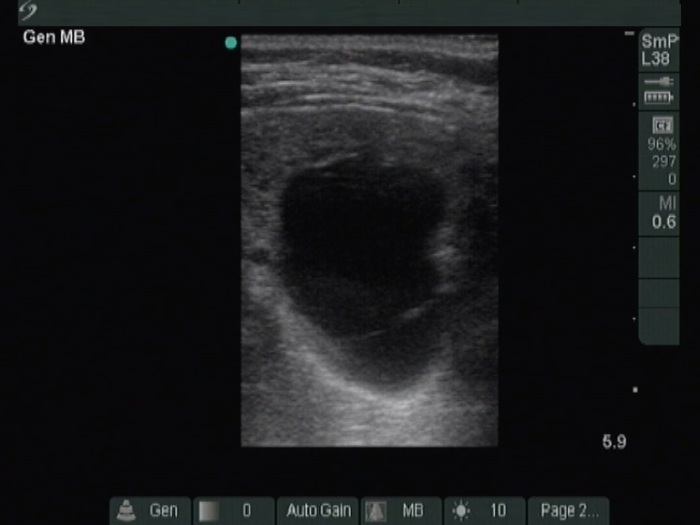

Ultrasonography. The thyroid was moderately hypoechoic. A large cystic nodule occupied great part of the right lobe. There was a moderately hypoechoic solid nodule in the lower third of the right lobe. This lesion presented with taller-than-wide and taller-than-long shape and had both perinodular and intranodular vascularity.

Fifteen mL yellow fluid was removed from the cystic nodule. Cytology resulted in non-diagnostic cystic lesion.